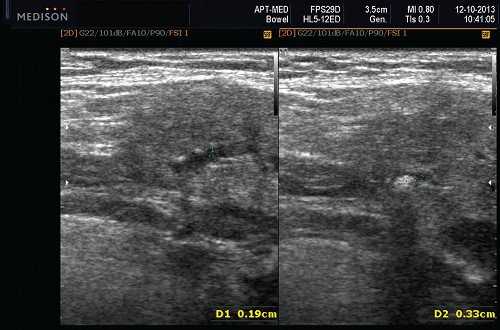

Данные УЗИ слюнных желез при карциноме

- Увеличенное солидное образование околоушной при ультразвуковом сканировании (примерно 75%) или поднижнечелюстной железы (примерно 25%)

- Особенности визуализации неспецифические

- Нечеткие или четко определенные границы.

- Гипоэхогенная, гомогенная или гетерогенная эхоструктура на УЗИ

- Отмечается внутренняя васкуляризация на цветном доплеровском исследовании.

- Могут наблюдаться аномальные интрапаротидные, перипаротидные, шейные лимфатические узлы.

Общие характеристики при ультразвуковом сканировании

- Лучший диагностический признак на УЗИ слюнной железы - Увеличенное солидное образование околоушной или поднижнечелюстной железы

- Размер 1-5 см.

Результаты ультразвукового исследования слюнной железы

- Серошкальное УЗИ. Одиночное солидное образование в паренхиме околоушной или подчелюстной железы. Может иметь хорошо выраженные, дольчатые или плохо очерченные / инфильтративные границы. Гипоэхогенная структура по отношению к паренхиме слюнной железы. Общее улучшение ультразвукового изображения задних структур. Иногда центральный кистозный компонент представляет некроз. Могут наблюдаться связанные аномальные интрапаротидные, перипаротидные, шейные лимфатические узлы

- Цветной допплер. Внутриузловая васкуляризация от умеренной до выраженной